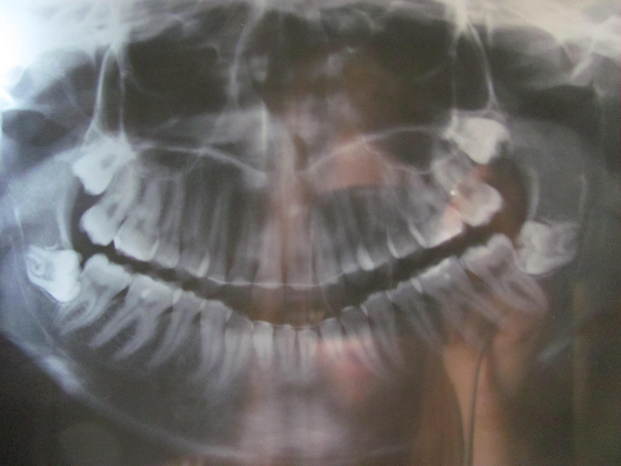

La radiografia dei miei denti. Per farla vedere bene l'ho messa sulla finestra, ma si vede l'alberello dietro XDD

Come vedete è così da tutti e due i lati. E sopra non sono messa meglio.